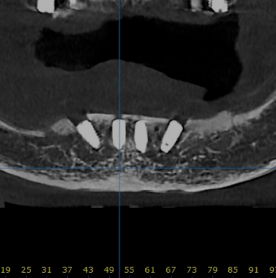

대부분 앞쪽에는 뼈가 있어서

틀니 오래 끼신 분도

이렇게 기존에서 심으면 가능한 경우가 많아요

더군다나 디지털 가이드를 이용해서

뼈가 얇은 경우에도 정확하게 심을 수 있어요